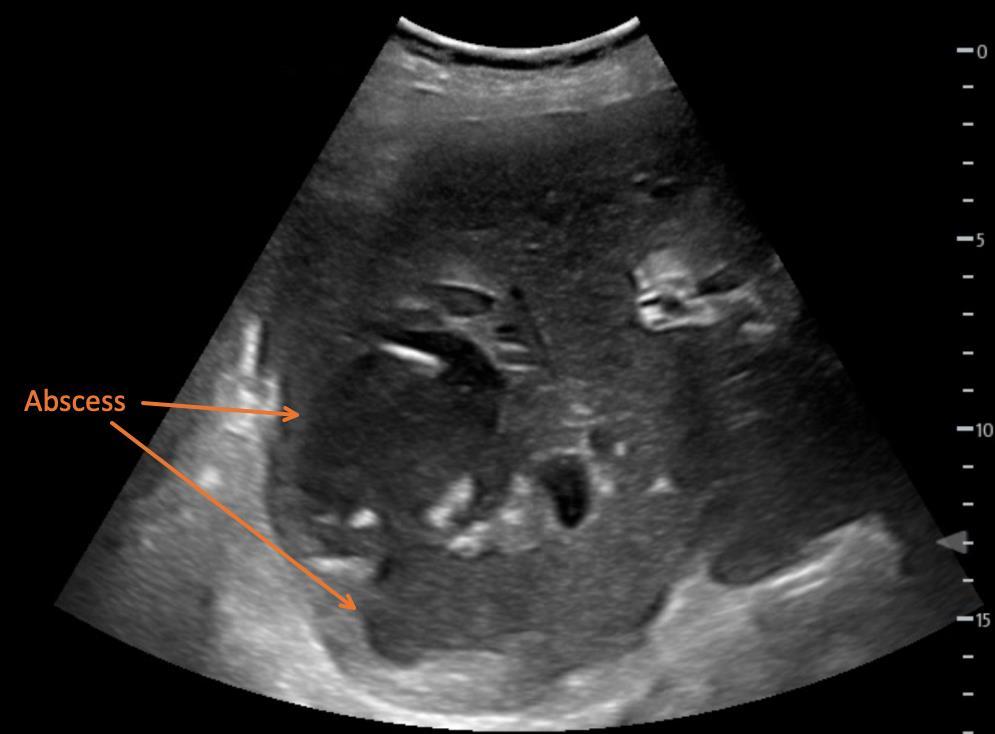

Case Series: This paper describes three cases, all of which consist of a painful complaint in the thoracic region. The first was a patient diagnosed with a breast abscess. The second patient was diagnosed with breast cellulitis. Finally, the third patient was diagnosed with a large breast abscess that extended into the axilla. All three sustained immense relief with the pectoralis block.

CASE SERIES

A 23-year-old pregnant woman presented to the ED with pain and swelling in her left breast. She had a known history of breast cancer and had been seen by her breast surgeon four days prior for mild redness. She had been placed on cephalexin without relief. A point-of-care ultrasound revealed a threecentimeter (cm) abscess on the medial aspect of her breast. The patient’s vital signs were unremarkable other than a mild tachycardia of 110 beats per minute. The surgical service came to the bedside to evaluate the patient and asked for procedural sedation for drainage. Because of ED crowding, the physician opted for a Pecs I block at the bedside with 15 mL of 0.25% ropivacaine. About 30 minutes after completion of the block, five mL of 1% lidocaine with epinephrine was used to anesthetize the skin over the abscess. The surgical team performed a bedside incision and drainage, removing 10 mL of purulent material. The patient was observed in the ED for 24 hours and then discharged with close, outpatient follow-up.